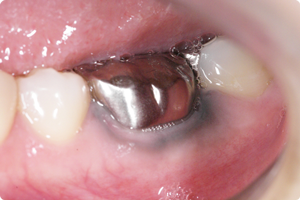

メタルタトゥーという言葉をご存知ですか??

金属の被せ物や土台(※メタルコア)などの金属が錆びて溶け出して歯肉に沈着し、歯ぐきが黒く変色してしまうものです。

メタルタトゥー=「金属の刺青」ともいわれるように、多くの場合歯肉の奥深くまで金属イオンが浸透しているため、簡単に除去できないことが多く、外科的にメスなどで切り取る手術が必要になります。これを防ぐには、一切の金属を使用しないことが必要です。